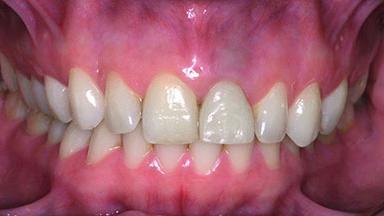

Replacement of a Perforated Upper Left Central Incisor: Early Placement of an RC Bone Level Implant